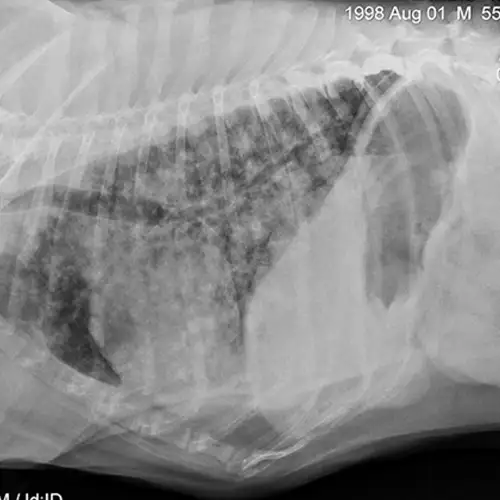

Mixed cardiac and pulmonary disease can exist in small animals with respiratory distress. For example, a dog may be presented with a history of mitral valve insufficiency but have clinical and radiographic evidence of aspiration pneumonia following a dental prophylaxis; or, a cat may present with a heart murmur and evidence of lower airway disease based on breathing pattern and thoracic radiographs (Figure 4; see image gallery above).